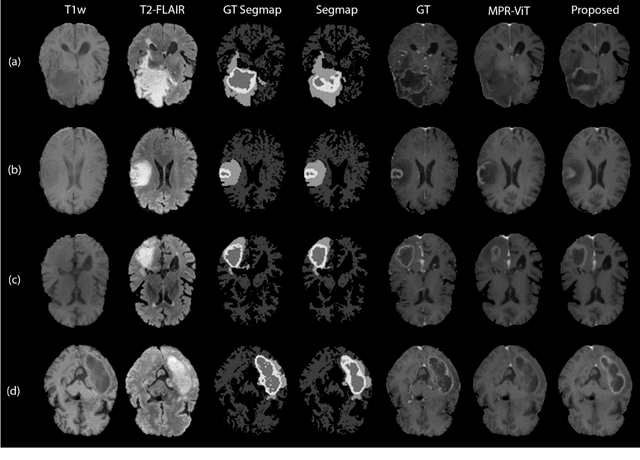

Abstract:Objective: Gadolinium-based contrast agents (GBCAs) are commonly used in MRI scans of patients with gliomas to enhance brain tumor characterization using T1-weighted (T1W) MRI. However, there is growing concern about GBCA toxicity. This study develops a deep-learning framework to generate T1-postcontrast (T1C) from pre-contrast multiparametric MRI. Approach: We propose the tumor-aware vision transformer (TA-ViT) model that predicts high-quality T1C images. The predicted tumor region is significantly improved (P < .001) by conditioning the transformer layers from predicted segmentation maps through adaptive layer norm zero mechanism. The predicted segmentation maps were generated with the multi-parametric residual (MPR) ViT model and transformed into a latent space to produce compressed, feature-rich representations. The TA-ViT model predicted T1C MRI images of 501 glioma cases. Selected patients were split into training (N=400), validation (N=50), and test (N=51) sets. Main Results: Both qualitative and quantitative results demonstrate that the TA-ViT model performs superior against the benchmark MRP-ViT model. Our method produces synthetic T1C MRI with high soft tissue contrast and more accurately reconstructs both the tumor and whole brain volumes. The synthesized T1C images achieved remarkable improvements in both tumor and healthy tissue regions compared to the MRP-ViT model. For healthy tissue and tumor regions, the results were as follows: NMSE: 8.53 +/- 4.61E-4; PSNR: 31.2 +/- 2.2; NCC: 0.908 +/- .041 and NMSE: 1.22 +/- 1.27E-4, PSNR: 41.3 +/- 4.7, and NCC: 0.879 +/- 0.042, respectively. Significance: The proposed method generates synthetic T1C images that closely resemble real T1C images. Future development and application of this approach may enable contrast-agent-free MRI for brain tumor patients, eliminating the risk of GBCA toxicity and simplifying the MRI scan protocol.

Abstract:Purpose: Apparent diffusion coefficient (ADC) maps derived from diffusion weighted (DWI) MRI provides functional measurements about the water molecules in tissues. However, DWI is time consuming and very susceptible to image artifacts, leading to inaccurate ADC measurements. This study aims to develop a deep learning framework to synthesize ADC maps from multi-parametric MR images. Methods: We proposed the multiparametric residual vision transformer model (MPR-ViT) that leverages the long-range context of ViT layers along with the precision of convolutional operators. Residual blocks throughout the network significantly increasing the representational power of the model. The MPR-ViT model was applied to T1w and T2- fluid attenuated inversion recovery images of 501 glioma cases from a publicly available dataset including preprocessed ADC maps. Selected patients were divided into training (N=400), validation (N=50) and test (N=51) sets, respectively. Using the preprocessed ADC maps as ground truth, model performance was evaluated and compared against the Vision Convolutional Transformer (VCT) and residual vision transformer (ResViT) models. Results: The results are as follows using T1w + T2-FLAIR MRI as inputs: MPR-ViT - PSNR: 31.0 +/- 2.1, MSE: 0.009 +/- 0.0005, SSIM: 0.950 +/- 0.015. In addition, ablation studies showed the relative impact on performance of each input sequence. Both qualitative and quantitative results indicate that the proposed MR- ViT model performs favorably against the ground truth data. Conclusion: We show that high-quality ADC maps can be synthesized from structural MRI using a MPR- VCT model. Our predicted images show better conformality to the ground truth volume than ResViT and VCT predictions. These high-quality synthetic ADC maps would be particularly useful for disease diagnosis and intervention, especially when ADC maps have artifacts or are unavailable.